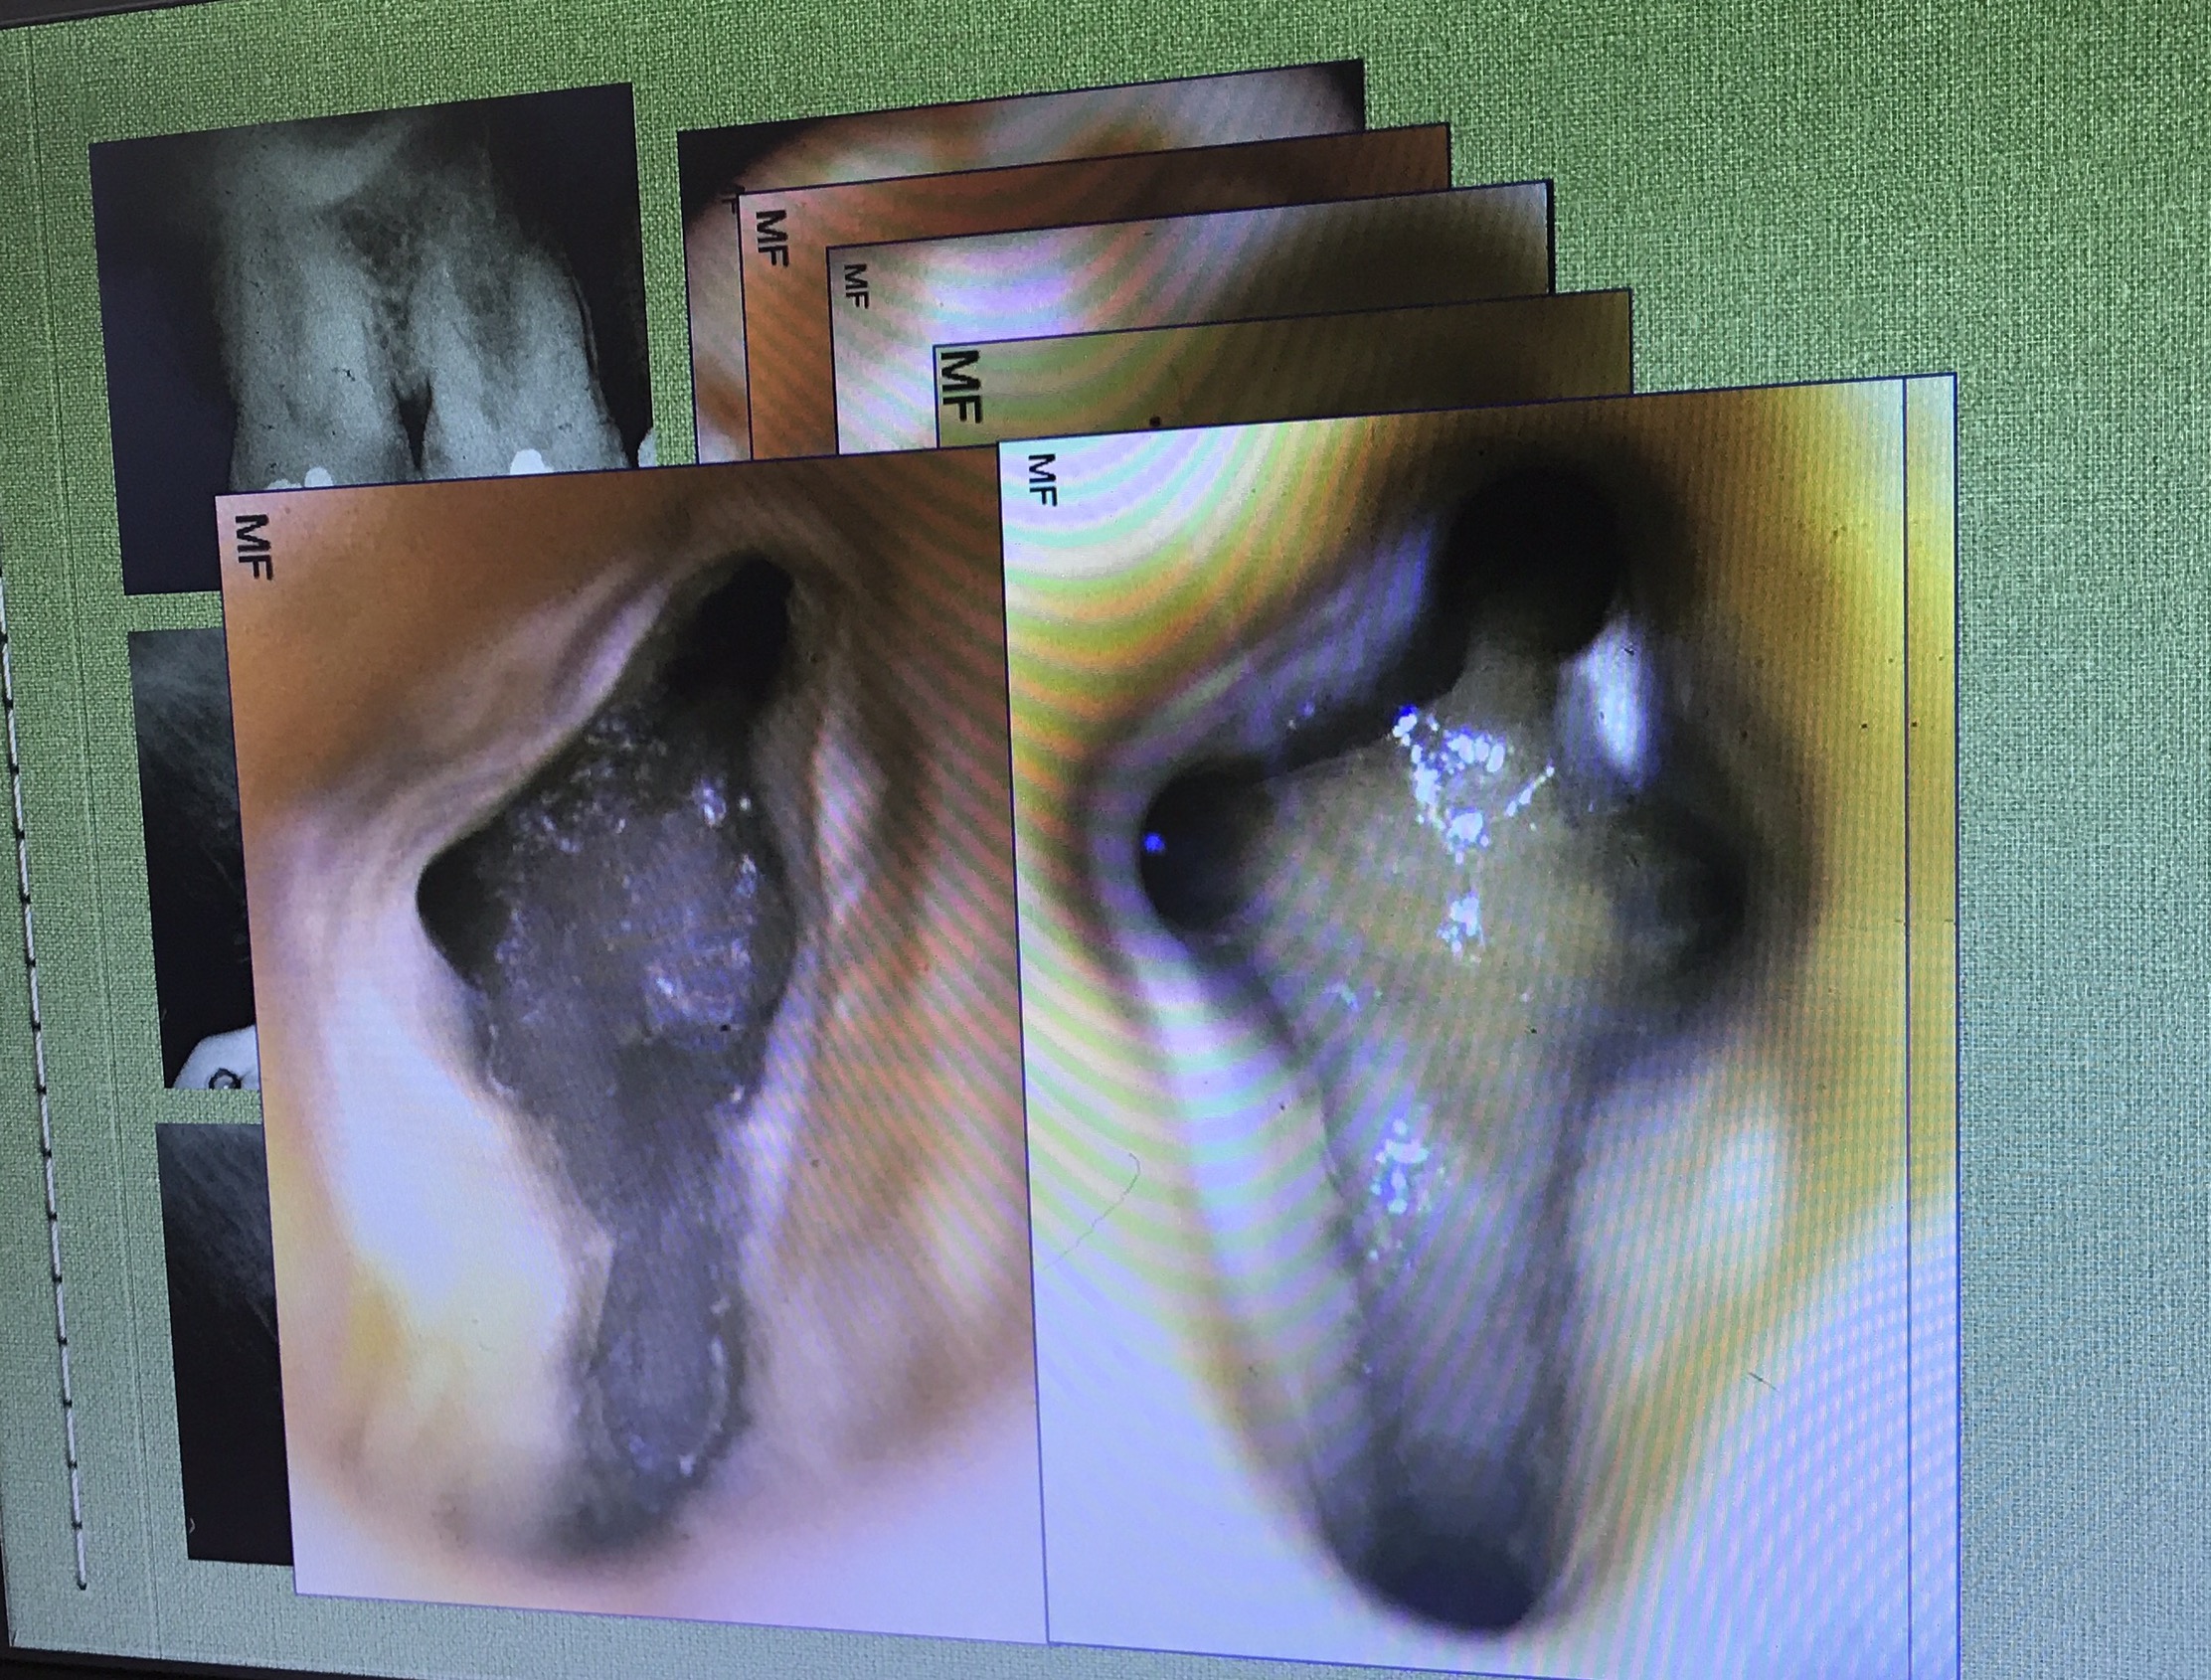

งานที่ใช้เยอะมาก การ Locate canal หา MB2

อย่างที่บอก ท่านอาจารย์แนะนำว่า ควรมี Mind set ไว้ในใจว่า ฟัน molar บน จะมี MB2 อยู่ในตำแหน่งที่ค่อนมาทาง Palatal ต่อ MB1 เล็กน้อย

ตำแหน่ง MB2 จะห่างจาก MB1 ไม่มาก

อันนี้ใช้วิธีดูจากฟองอากาศขณะ IR ที่เกิดบริเวณ orifice ครับ

กฎในการหาตำแหน่งจาก paper นี้ครับ

ทิศทางการกรอ จะไม่ remove ส่วน floor ครับ แต่กำจัดเฉพาะส่วนที่ Calcified

ลองสังเกตเส้นที่ลาก ตำแหน่งของ MB2 จะอยู่ mesial ต่อเส้นนี้ที่ระยะประมาณ 1-2.5 มม.

แนวเส้นประสีแดง คือ บริเวณที่จะพบ MB2